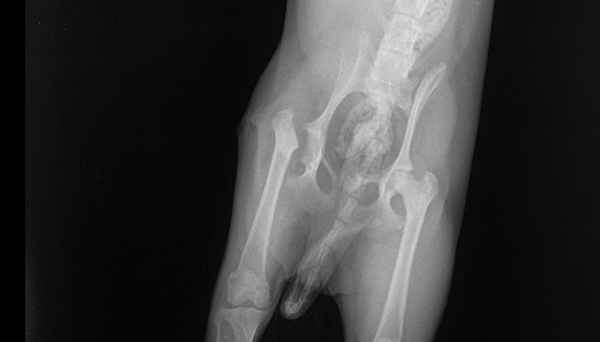

Рентгенограмма собаки с болезнью Легга-Пертеса до операции и после выполненной резекционной (отсекающей) артропластики